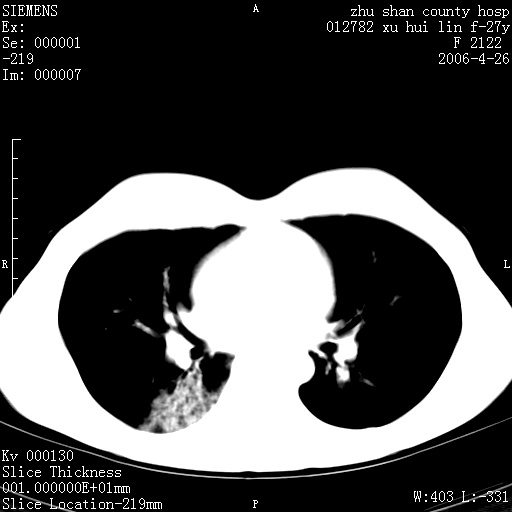

女性 病人 27岁!本院职工家属,五月前因感冒透视发现病变,ct示:左肺下叶背段感染性病变。经过半月规范抗生素治疗后复查病变无明显变化,后行四月规范抗痨治疗,复查无明显变化,后复查无效!请大家帮忙看看!

右肺下叶背段见片状高密度区,边界不清,密度不均,无钙化及空洞影,背段支气管通畅。所见层面肺门及纵隔内未见明显肿大淋巴结影。

女性 病人 27岁!本院职工家属,五月前因感冒透视发现病变,ct示:左肺下叶背段感染性病变。经过半月规范抗生素治疗后复查病变无明显变化,后行四月规范抗痨治疗,复查无明显变化,后复查无效!

诊断:首先还是考虑为慢性炎症。

结核虽然好发于下叶背段,但周围无明显卫星灶,化验结果怎样?